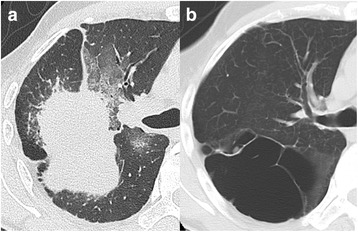

Computed tomography (CT) demonstrated a well-circumscribed mass measuring 7.0 × 6.5 × 6.0 cm accompanying a reticular shadow in the right upper lobe, with multiple emphysematous bullae in the bilateral upper sides of the lung (Fig. 1a). Chest magnetic resonance imaging revealed a mass with heterogeneous attenuation. One year previously, the patient had undergone CT after complaining of shortness of breath (Fig. 1b). The previous CT showed a giant bulla without any wall thickening in the right upper lobe. Based on a comparison of the image findings and his clinical history, an acute hemorrhage was suspected to have occurred inside the bulla; there were no CT findings that were suggestive of a malignant tumor. The initial treatment was percutaneous trans-catheter embolization of the feeding bronchial artery of the mass. Surgery was planned after the initial treatment failed to control his hemoptysis.

Fig. 1.

a A solitary mass in the right upper lobe of the lung. The mass was well-circumscribed and surrounded by a reticular shadow. The average HU value of the mass on HRCT was 35. b An emphysematous giant bulla of the lung was observed 1 year before the hemorrhagic presentation of the tumor